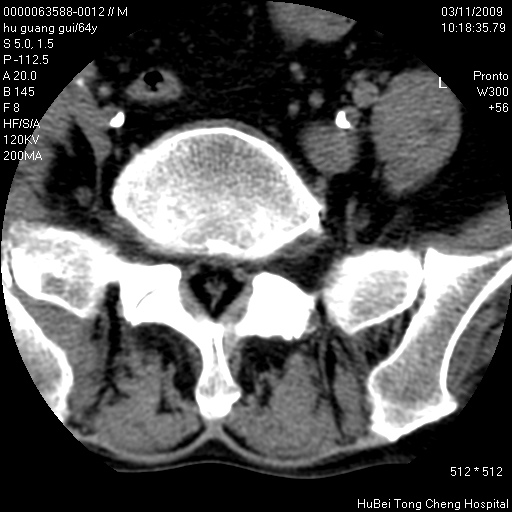

患者 男,64岁。腰痛十余天。(临床未提供其他病史)

临床诊断:腰痛原因待查(腰椎间盘突出症?)。

腰椎间盘ct轴位平扫(层厚5mm,层距4mm),图像如下:

腰椎退行性变,腰4—5椎间盘膨出。

右侧骶骨侧块骨侵蚀,骶髂关节骨性关节面破坏,并见软组织肿块,考虑骨转移瘤可能,进一步检查。

1.腰椎退行性变,腰4—5椎间盘膨出。

2.右侧骶骨侧块骨侵蚀,骶髂关节骨性关节面破坏,并见软组织肿块,考虑:脊索瘤,骨转移瘤可能,进一步检查。

1)腰椎退行性变,l4—5椎间盘膨出。2)骶骨右侧块骨转移瘤可能,3)水平骶椎。建议作一步检查。